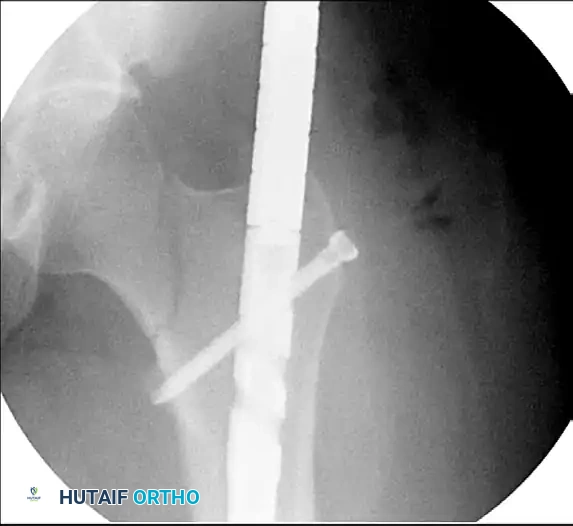

4. Once aligned, two cephalomedullary screws are placed into the femoral head.

Figure 55-63D: Intraoperative fluoroscopic view after removal of the standard proximal interlocking screw, adjustment of the nail, and successful placement of reconstruction screws.

If the nailing system does not allow for a reconstruction option, the surgeon must utilize a "miss-a-nail" technique. Multiple cannulated screws (typically 6.5mm or 5.0mm) are carefully placed around the intramedullary nail. This requires precise fluoroscopic guidance to ensure the screws pass anterior or posterior to the nail without compromising the fixation of either the neck or the shaft.